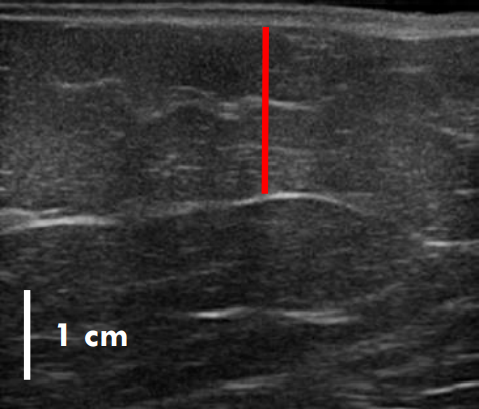

트루스컬프iD 시술 전 / 12주 후 초음파 사진 비교

트루스컬프 아이디 시술 전 / 12주 후 (초음파)

트루스컬프 아이디 시술 전, 12주 후 초음파를 비교한 사진입니다.

시술 전과 비교했을 때 약 36% 정도 지방이 감소한 효과를 볼 수 있는데요. 실제 운동으로 뱃살을 빼 본 분들이라면 아시겠지만 운동이나 식이요법으로 이 정도의 지방 감소 효과를 보려면 상당한 노력과 체계적인 관리를 필요로 하지요.